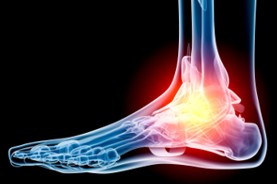

The Foot Institute is an association of Grande Prairie Doctors specializing in the medical treatment of the foot and ankle, and is one of the largest groups of foot specialists in Alberta.

The Grande Prairie Foot Institute is dedicated to the medical and surgical treatment of the foot. Our mandate is to provide the best possible medical, surgical and preventative treatment available for our patients. We do this by providing well-trained Doctors who are committed to treat and prevent all types of foot pain, biomechanical disorders, as well as all other problems relating to the feet.

At the Grande Prairie Foot Institute, our Doctors are trained to specifically treat problems associated with your feet or ankles. Below are several of the most common problems that we see on a day to day basis: